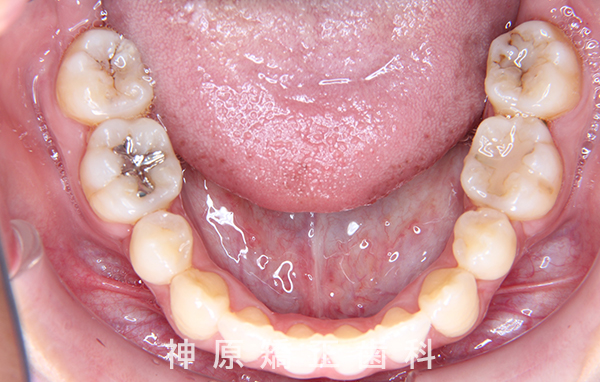

初診時

マルチブラケット装着1年後

治療終了

治療前と治療後

今回の矯正治療にあたり、矯正精密検査の結果をもとに診断を行いました。その結果、左下の永久歯が生まれつき欠損していました。歯並びの乱れや口元の突出感を改善するため、小臼歯と残っている乳歯を抜くことが必要だと判断しました。